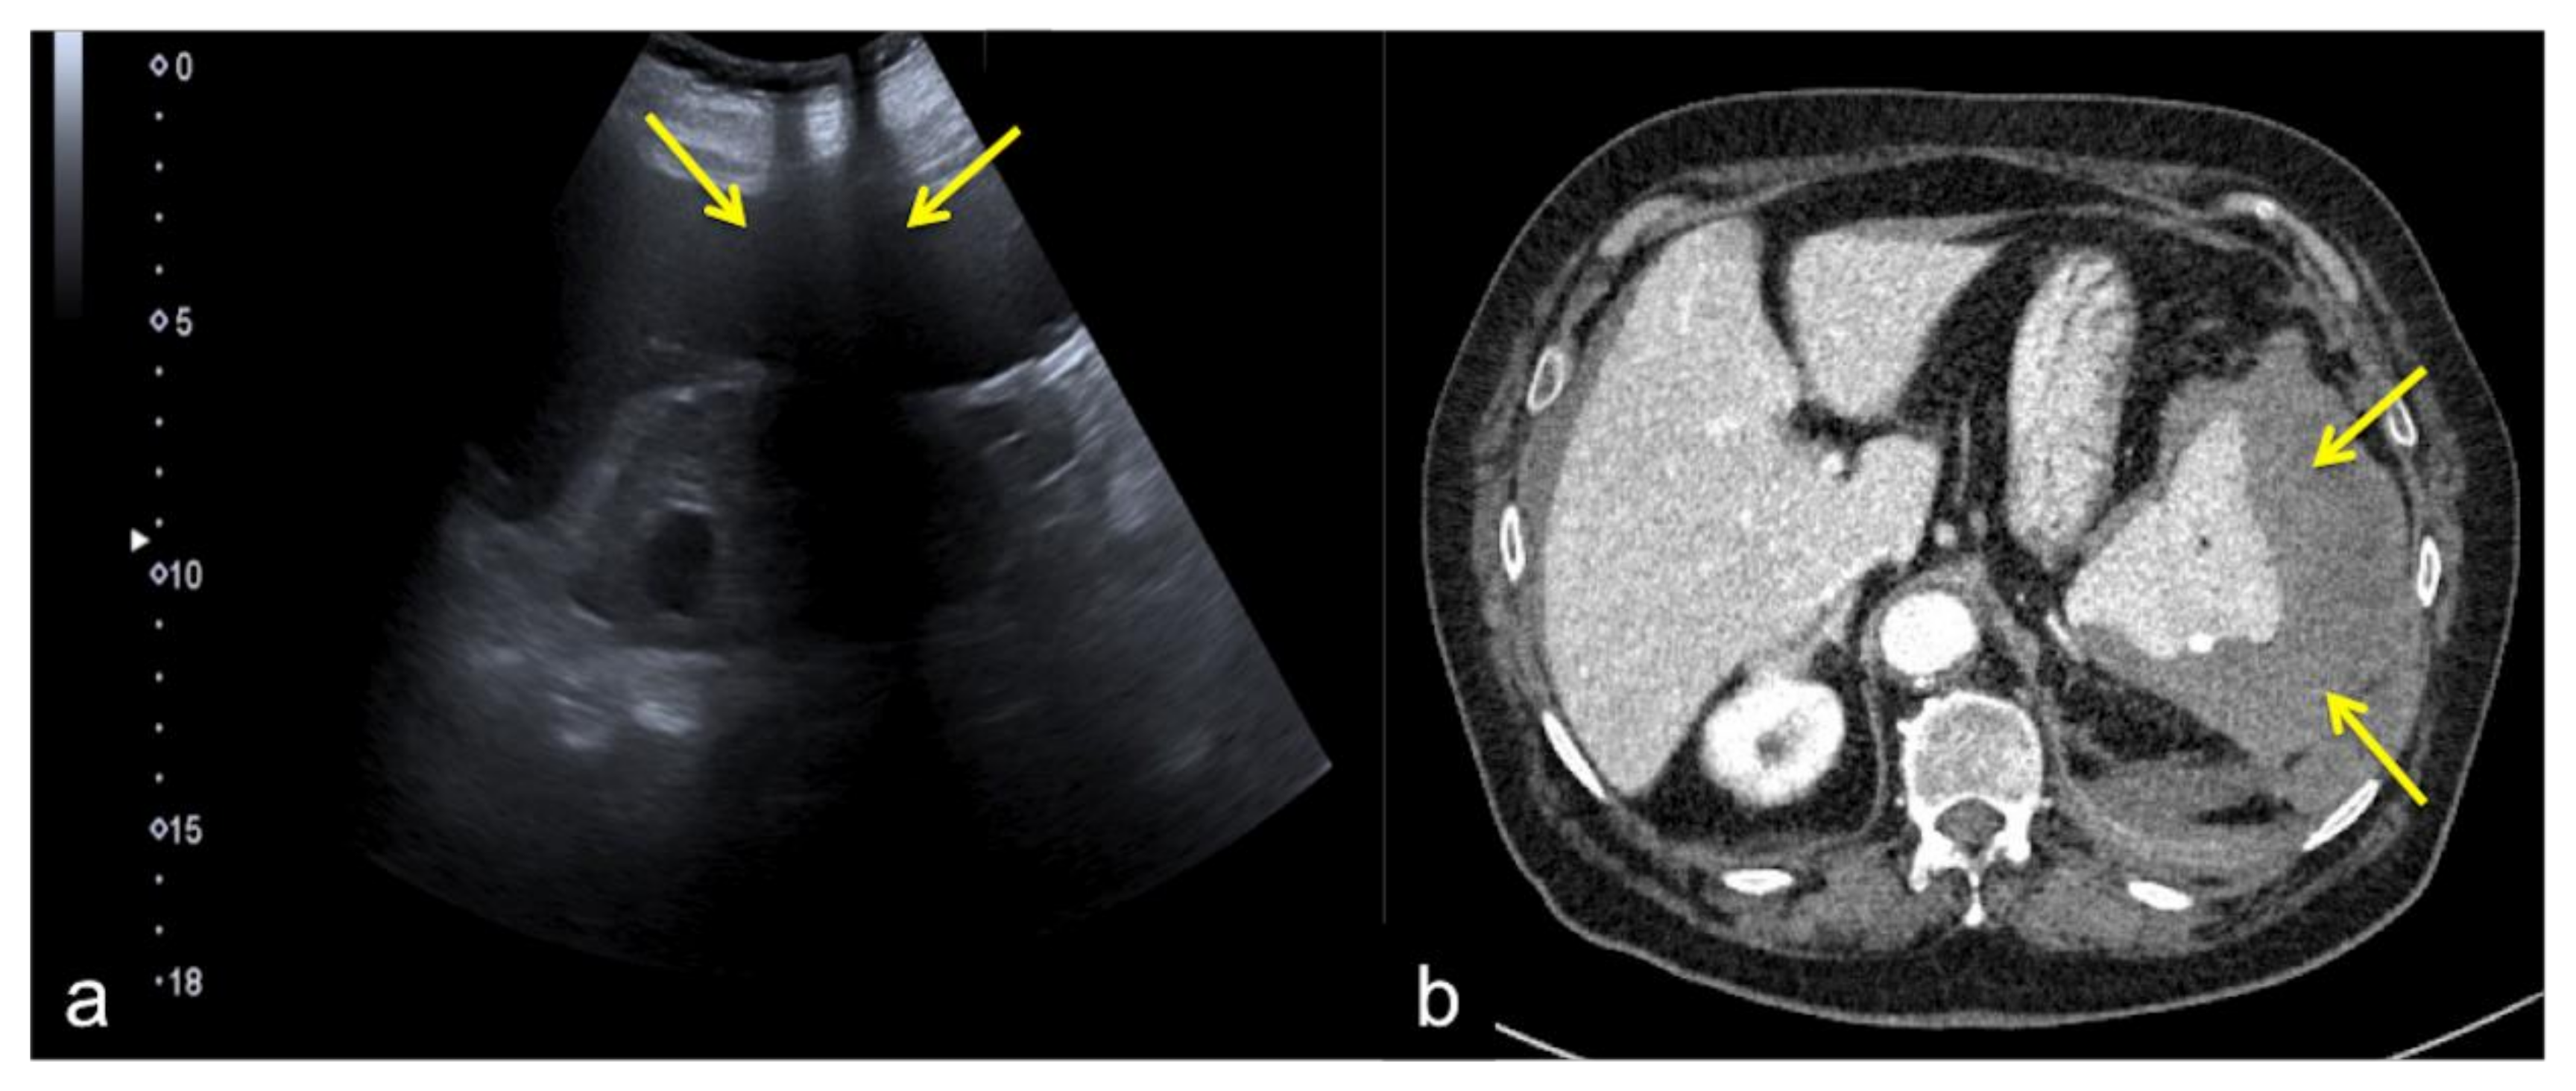

3.1.2. The Mirror-Imaging Effect